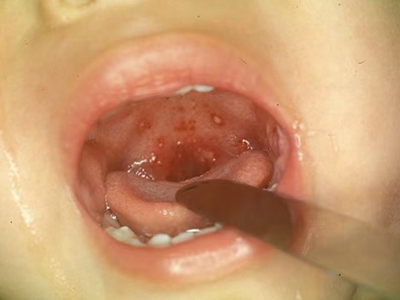

咽峡

水肿 · 水疱

小儿疱疹性咽峡炎咽峡部位有小水疱图

小儿疱疹性咽峡炎的患者咽峡部位有小水疱,小水疱表面发白,半球样凸起,水疱周围黏膜微微泛红,有轻微水肿,患者自觉咽喉部位有明显疼痛。